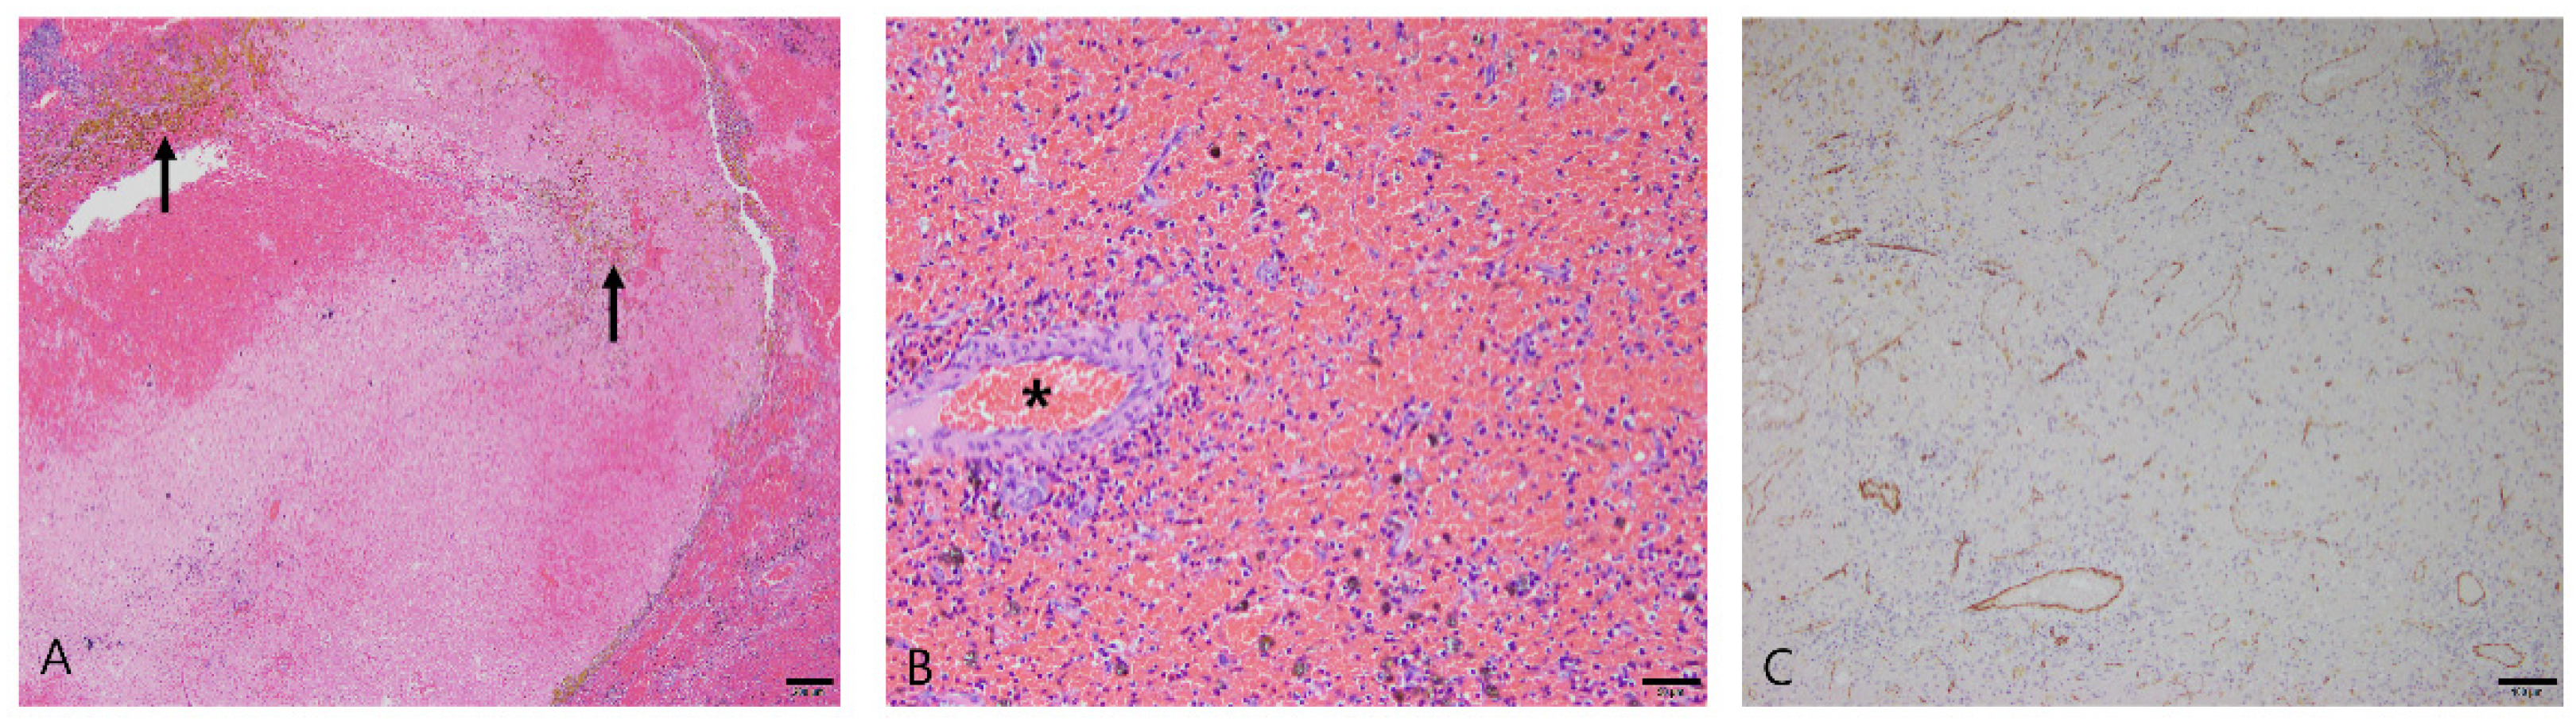

3.2.1. Nodular Hyperplasia

3.2.2. Hematoma

3.2.3. Splenic Hemangiosarcoma